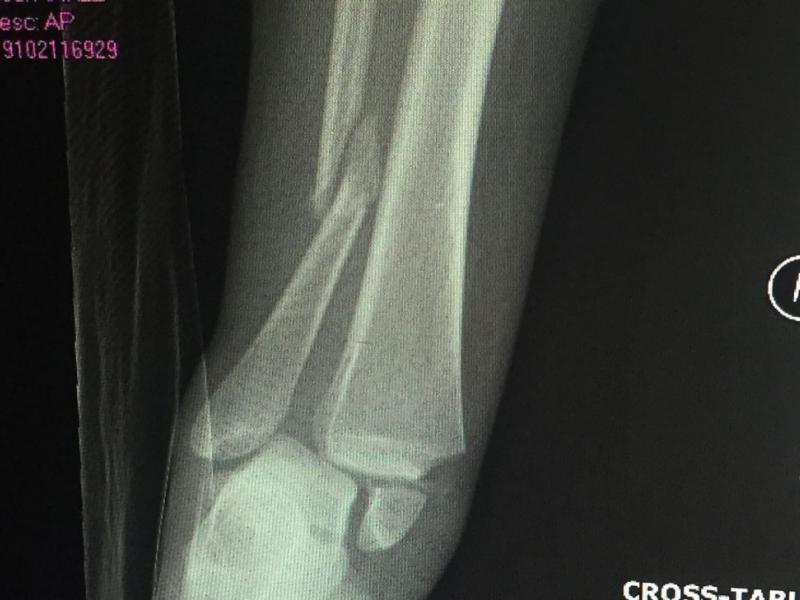

Junior Lainey Rickard and senior Laurie Segreaves have never met; they don't know each other; their teams have never played each other. However, both women share two vital things: they both play rugby and they are both coming back from injuries.

University of North Carolina, Charlotte's Lainey Rickard suffered a devastating injury last season.